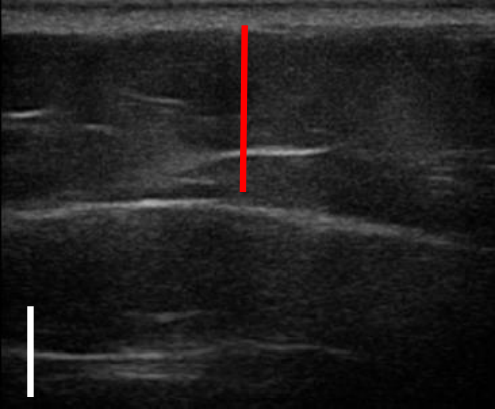

위 사례도 초음파 비교 사진을 보도록 할게요.

트루스컬프 아이디 시술 전, 12주 후

초음파를 비교한 사진입니다.

위 사례의 경우 지방량이 워낙 많다 보니 시술 후 겉으로 드러난 변화는 적었으나 실제로 감소한 지방량은 상당히 많았습니다.

시술 전과 비교했을 때 약 31% 정도 지방이 감소했습니다.

복부, 옆구리살이 너무 많은 경우 실제 눈에 보이는 것보다 내부에 쌓여있는 지방이 두터운 경우가 많아 시술을 해도 큰 변화를 보이지 않는 경우가 많은데요. 실제로 시술 후 큰 변화가 없어 실망하는 분들도 많지만 위와 같이 초음파 검사를 통해 속을 들여다보면 상당 부분 지방이 감소한 것을 확인할 수 있습니다.